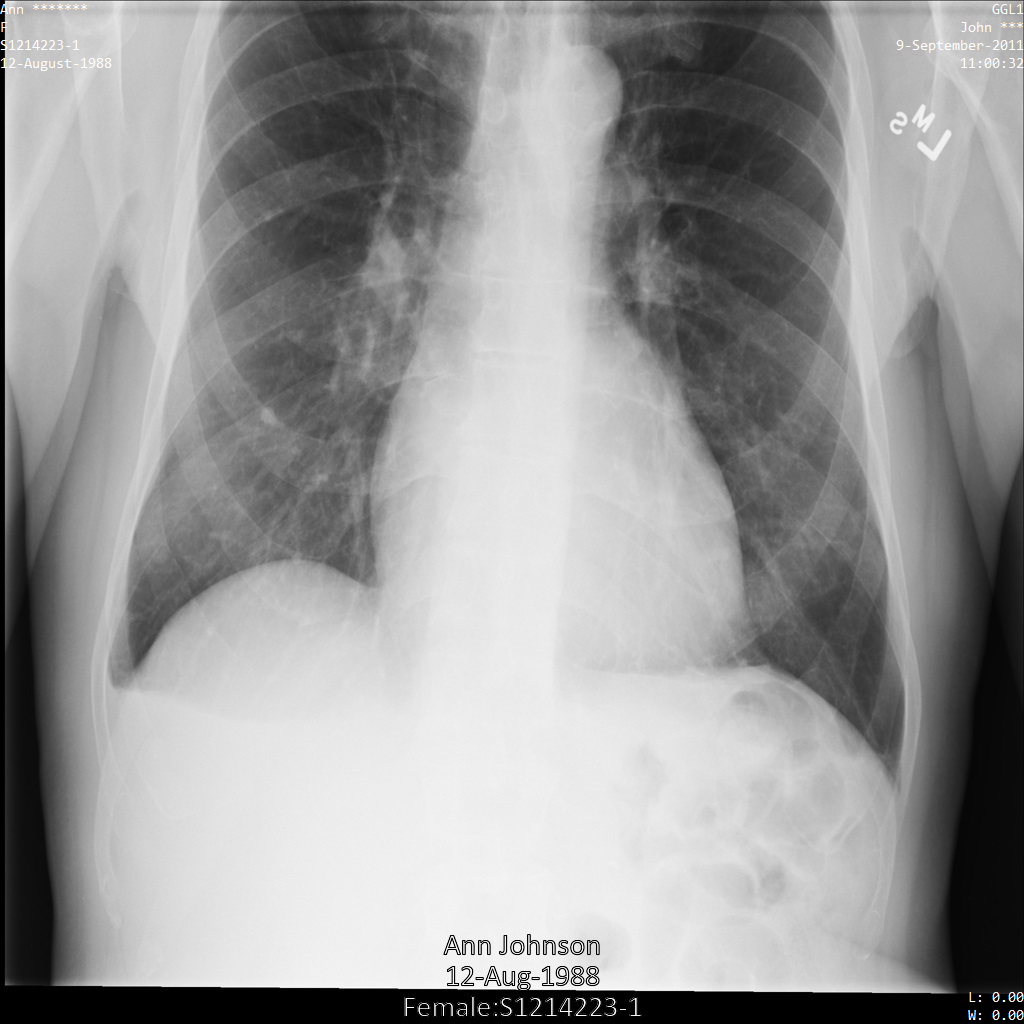

使用 ATTRIBUTE_CONFIDENTIALITY_BASIC_PROFILE 標記篩選設定檔將圖片提交給 Cloud Healthcare API 後,圖片看起來會如下所示。雖然圖片頂端角落顯示的中繼資料已遭塗銷,但圖片底部的 PHI 仍會保留。如要一併移除內建文字,請參閱「從圖片中遮蓋內建文字」。

使用 REDACT_ALL_TEXT 和 DEIDENTIFY_TAG_CONTENTS 選項將圖片提交給 Cloud Healthcare API 後,圖片看起來會如下所示。請注意下列異動:

- 圖片左上角和右上角的名稱已使用

CryptoHashConfig轉換 - 圖片左上角和右上角的日期已使用

DateShiftConfig轉換 - 圖片底部的內建文字已經過編輯

使用 DEIDENTIFY_TAG_CONTENTS 設定檔將圖片提交給 Cloud Healthcare API 後,圖片看起來會如下所示。

請注意下列異動:

- 圖片左上角和右上角的名稱已使用

CryptoHashConfig轉換 - 圖片左上角和右上角的日期已使用

DateShiftConfig轉換

使用 redactConfig 轉換將圖片提交給 Cloud Healthcare API 後,圖片看起來會如下所示:

使用 characterMaskConfig 轉換將圖片提交給 Cloud Healthcare API 後,圖片看起來會如下所示:

使用 dateShiftConfig 轉換將圖片提交給 Cloud Healthcare API 後,圖片看起來會如下所示:

使用 cryptoHashConfig 轉換將圖片提交給 Cloud Healthcare API 後,圖片看起來會如下所示:

使用 replaceWithInfoTypeConfig 轉換將圖片提交給 Cloud Healthcare API 後,圖片看起來會如下所示: